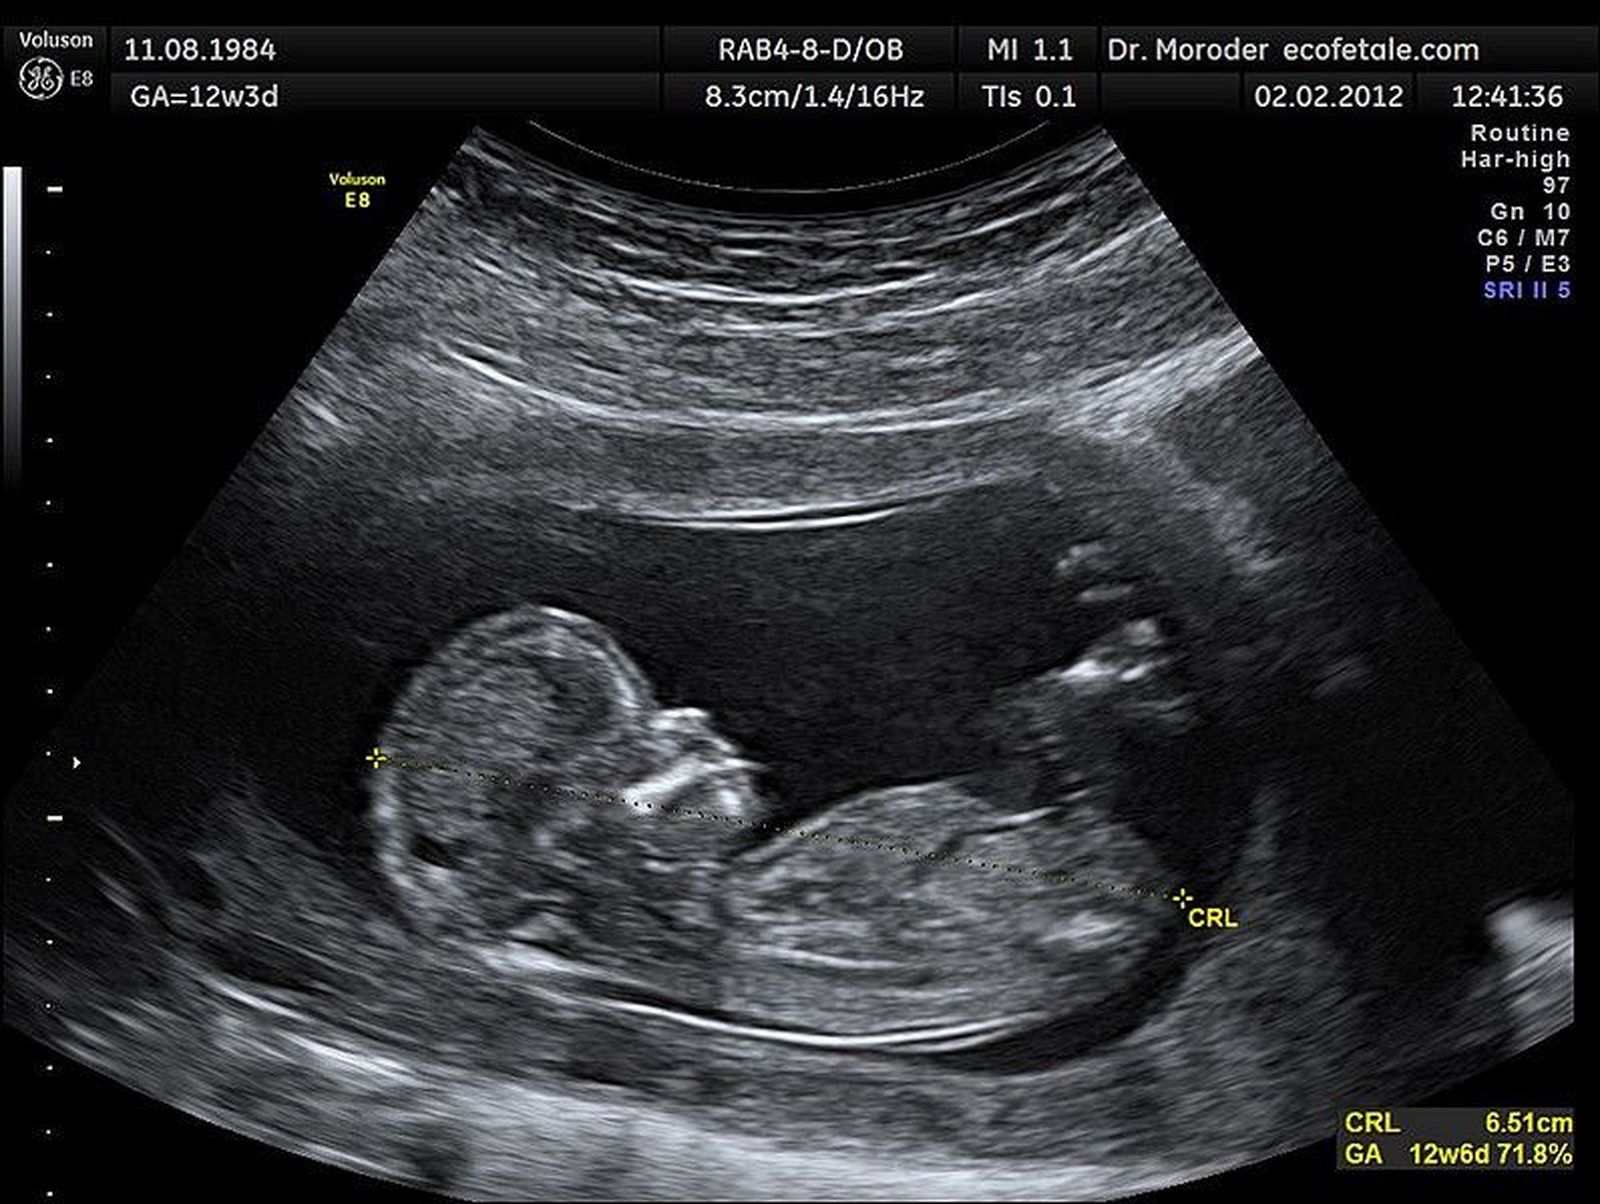

Ecografía

Durante el embarazo cualquier cuestión de salud de la madre pasa a ser doblemente importante. Es el caso de un simple resfriado. Cuando ocurre durante un embarazo, el virus puede propagarse a la placenta y, por tanto, contagiarse al feto.